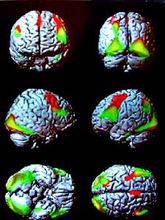

语言中枢两侧大脑皮层功能相关

大脑皮层的语言中枢

人类大脑皮层一定区域的损伤,可以引致特有的各种语言活动功能障碍。临床发现,损伤布洛卡(Broca)三角区,会引致运动失语症(motoraphasia)。病人可以看懂文字与听懂别人谈话,但自己却不会讲话,不能用语词来口头表达;然而,其与发音有关的肌肉并不麻痹,就是不能用“词”来表达自己的意思。损伤额中回后部接近中央前回手部代表区的部位,则病人可以听懂别人的谈话,看懂文字,自己也会讲话,但不会书写;然而,其手部的其他运动并不受影响,这种情况称为失写症(agraphia)。颞上回后部的损伤,会引致感觉失语症(sensoryaphasia),病人可以讲话及书写,也能看懂文字,但听不懂别人的谈话;事实上,病人能听到别人的发音,就是不懂其含义,但其视觉却是良好的,其他的语言活动功能仍健全,这种情况称为失读症(alexia),因此,语言活动的完整功能是与广大皮层区域的活动有关的,各区域的功能是密切相关的。严重的失语症可同时出现上述四种语言活动功能的障碍。2

一侧优势

一侧优势是指人类的脑的高级功能向一侧半球集中的现象;左侧半球在语词活动功能上占优势,右侧半球在非语词性认识功能止占优势。但是,这种优势感是相对的,而不是绝对的;因为左侧半球也有一定的非语词性认识功能,右侧半球也有一定的简单的语词活动功能。 产生上述各种语言活动功能障碍时,在一般运用右手劳动为主的成年人中,其大脑皮层损伤经常发生在左侧。因为绝大多数用右手劳动为主的成年人,右侧大脑皮层的44区的损伤并不发生明显的语言活动障碍;然而其左侧大脑皮层布洛卡的损伤,则可形成严重的运动失语症,这种左侧大脑皮层的语言活动功能上占优势的现象,反映了人类两侧大脑半球功能是不对等的,这种一侧优势的现象仅在人类中具有。